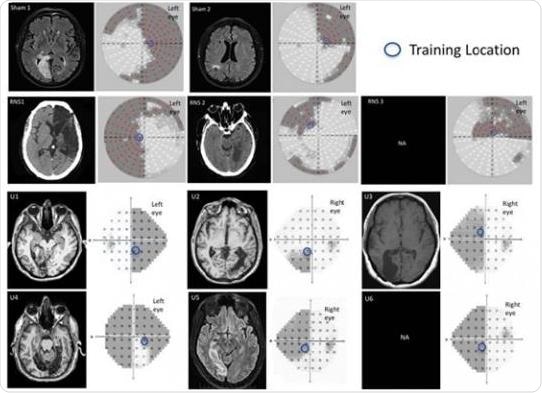

Neuroradiological images and visual perimetries of CB patients. All patients sustained damage of early visual areas or the optic radiations resulting in homonymous visual field defects as shown by the visual field perimetries, next to each brain image. Credit: Herpich et al., JNeurosci (2019)

By extending their findings to patients who suffered a stroke or traumatic brain injury affecting their visual cortex, the researchers suggest this safe and painless two-pronged approach could lead to faster visual recovery and improved quality of life for this underserved patient population.